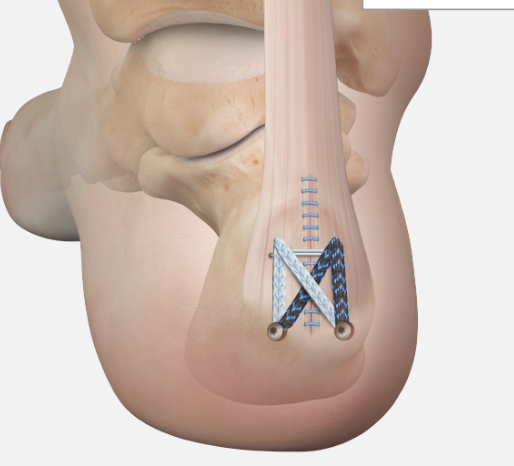

Arthrex - Achilles SpeedBridge™ System

Arthrex speedbridge system